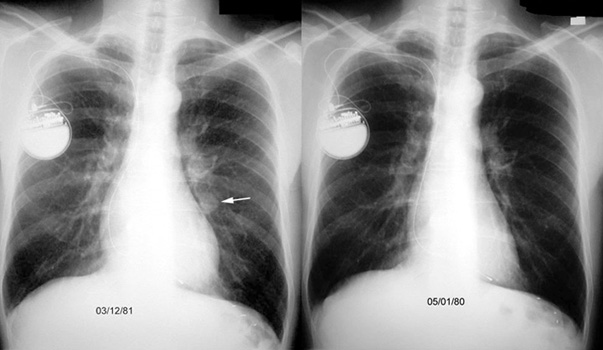

- Note the solitary pulmonary nodule.

- The film on the right is an old x-ray. The lesion was not present one year ago.